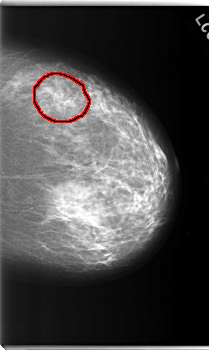

C_0207_1.LEFT_CC

LEFT_CC LINES 5944 PIXELS_PER_LINE 3552 BITS_PER_PIXEL 12 RESOLUTION 50 OVERLAY

FILE: C_0207_1.LEFT_CC.OVERLAY

TOTAL_ABNORMALITIES 1

ABNORMALITY 1

LESION_TYPE CALCIFICATION TYPE PLEOMORPHIC DISTRIBUTION CLUSTERED

LESION_TYPE MASS SHAPE IRREGULAR MARGINS SPICULATED

ASSESSMENT 4

SUBTLETY 4

PATHOLOGY MALIGNANT

TOTAL_OUTLINES 1

BOUNDARY